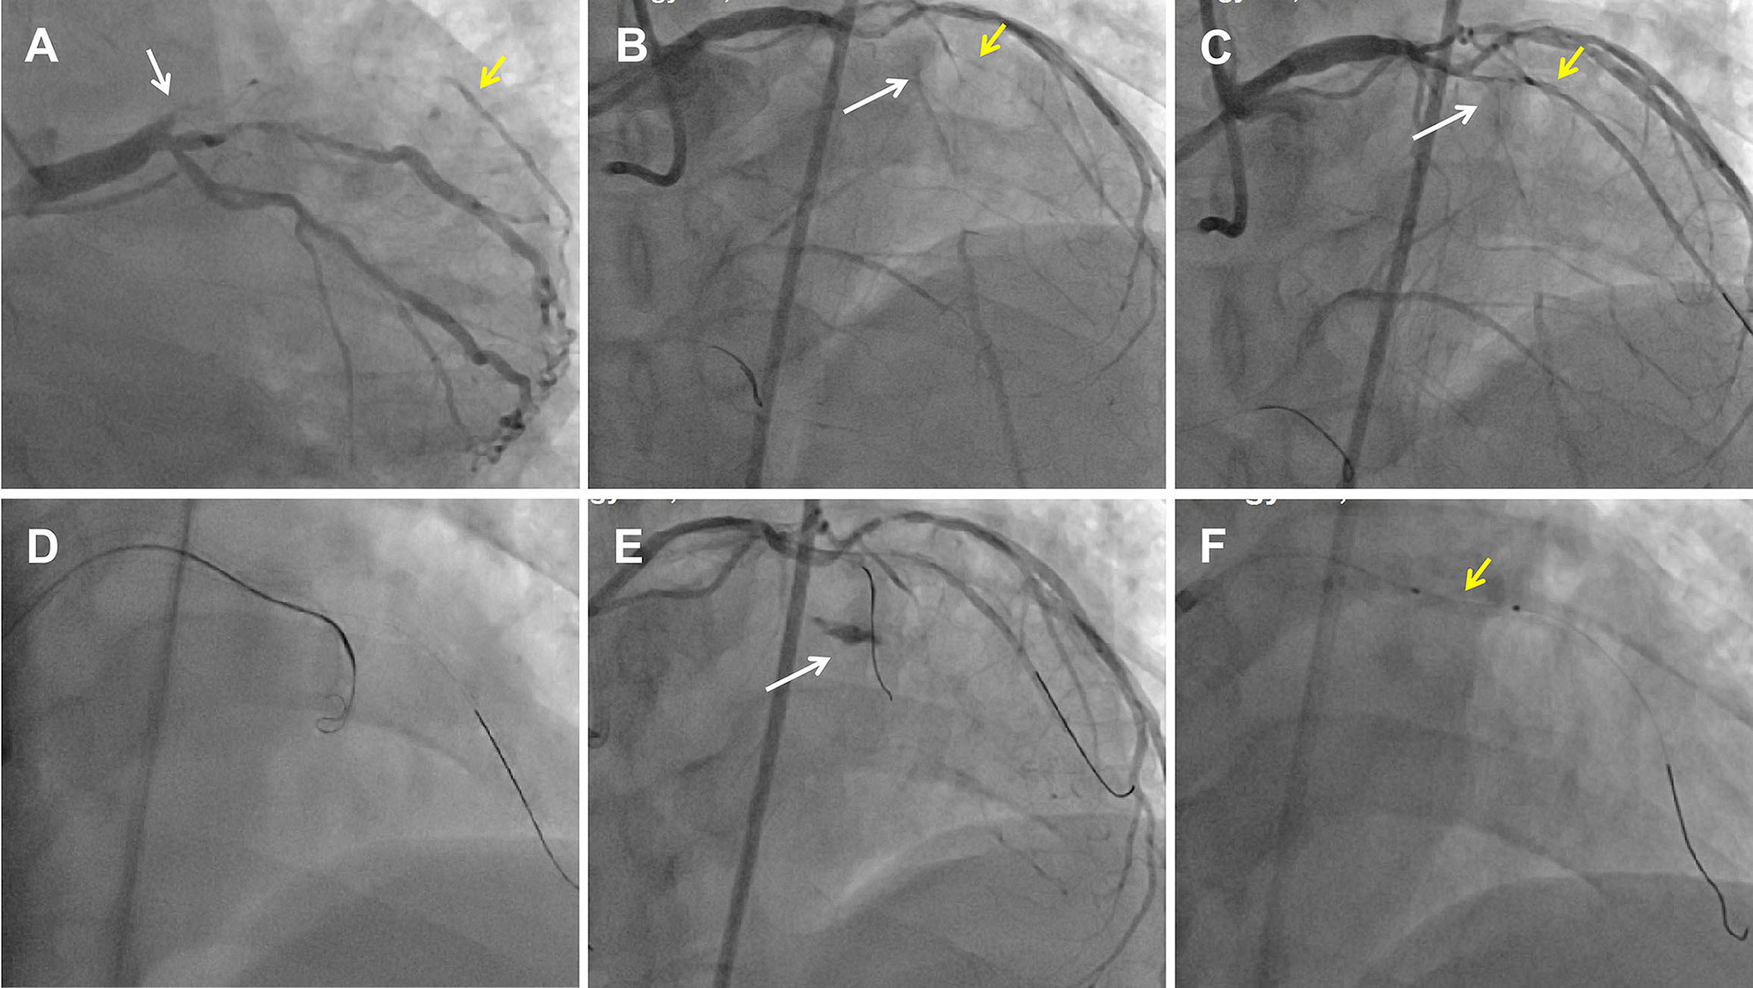

Figure 1

Perforation formation after an antegrade attempt during LAD CTO recanalization. (A) CAG showed a LAD CTO lesion with a stump (white arrow) and a D1 vessel (yellow arrow) filling by ipsilateral vessels. (B) Dual CAG showed middle LAD filling by collateral vessels from the RCA. The white arrow indicates the middle LAD, and the yellow arrow indicates the D1. (C) Pilot 200 wire into the distal true lumen of the D1 vessel. The white arrow indicates the mid-LAD segment, and the yellow arrow indicates the D1. (D) An antegrade Corsair catheter with a knuckled Pilot 200 wire was advanced into the supposed CTO body. (E) An Ellis type Ⅲ perforation occurred. The white arrow indicates contrast extravasation. (F) A proximal tamponade balloon (yellow arrow) from the D1 to the pro-LAD to control the perforation.

Dual angiography was performed and showed a proximal LAD CTO with a small stump, with ∼30 mm extending from the proximal to mid-LAD and several septal collaterals from the right coronary artery (RCA), and a good landing zone distal to the mid-LAD. Furthermore, it showed that the first large diagonal (D1) vessel was occluded within the LAD CTO lesion, and that two-thirds of its distal length was retrogradely filled via ipsilateral vessels, making it visualize as a larger vessel (Figure 1B, Supplementary Videos 1, 2). The primary antegrade approach was attempted with a Pilot 200 wire, which was successfully navigated into the distal true lumen of the D1 vessel (Figure 1C, Supplementary Video 3). After a 2.0 mm × 20 mm semi-compliant balloon dilation in the D1 vessel segment, dual CAG revealed that the LAD occlusion entry point was ambiguous. With the support of a dual lumen catheter (DLC), Gaia3 and Pilot 200 wires were used to explore the occlusion entrance, gaining access to the subintimal space. Subsequently, a knuckled Pilot 200 wire was tracked forward with a Corsair catheter, which appeared to be directed toward the septum rather than into the LAD course (Figure 1D, Supplementary Video 4), and intravascular ultrasound (IVUS) revealed that the entry point was incorrect. Next, several retrograde attempts were performed with softer wires such as SION/SION and Black/SUOH03 across the septal vessels, respectively, but these all failed. The following antegrade angiography revealed an Ellis type Ⅲ perforation (Figure 1E, Supplementary Video 5) located at the mid-LAD segment, which was likely caused by the knuckled Pilot 200 wire with the Corsair microcatheter tracking outside of the LAD architecture. Promptly, a 2.5 mm × 20 mm compliant balloon was used to tamponade from the D1 vessel to the proximal LAD and effectively controlled the pericardial bleeding (Figure 1F). In this situation, the retrograde approach was initiated again. The tip of the Sion wire, with a double-angled shape, crossed the RCA epicardial collateral vessel, which was connected to the septal vessels, as visualized by tip injection (Figure 2A, Supplementary Video 6). Stiffer wires, such as Pilot200/Gaia3, failed to penetrate the fibrous cap of the LAD CTO where it intersected with the D1 branch. Next, a knuckled Fielder XT-A wire was pushed forward into the LAD CTO body. Although reverse-controlled antegrade and retrograde tracking (r-CART) was performed, the UB3/Gaia3/CP12 stiffer wires all failed in the antegrade extension catheter (Figure 2B). Then, an antegrade parallel wire, with DLC support, was advanced as close as possible toward the retrograde wire (Figure 2C), and the extension catheter was subsequently delivered across the bifurcation, and successfully picked up the retrograde wire (Figure 2D). IVUS results, retracing from the D1 vessel to the LAD, confirmed that the retrograde wire entered the LAD vessel architecture through the outer edge of the calcification ring in the mid-LAD segment (Figure 3A), and from the LAD distal true lumen showed that the subintimal length was 18.2 mm (Figure 3B). To ensure adequate adhesion of the dissection flaps onto the perforation, multi-size balloon dilation for the D1 branch and the LAD, and 3.0 mm × 38 mm/3.5 mm × 38 mm DESs were deployed sequentially from the distal to the proximal LAD. IVUS was used to assess the optimal stent expansion and apposition. CAG showed that the perforation was completely sealed and there was thrombolysis in myocardial infarction (TIMI) grade III flow in the entire LAD (Figure 2E). Furthermore, the ostium of the D1 vessel was crushed, but good retrograde filling from the ipsilateral vessels was still observed (Figure 2F).